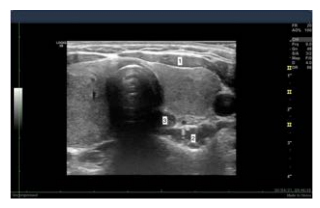

Observe a imagem a seguir, na qual se identificam três marcas anatômicas em uma ultrassonografia cervical.

Na imagem acima, os números 1, 2 e 3 correspondem, respectivamente, ao(à):